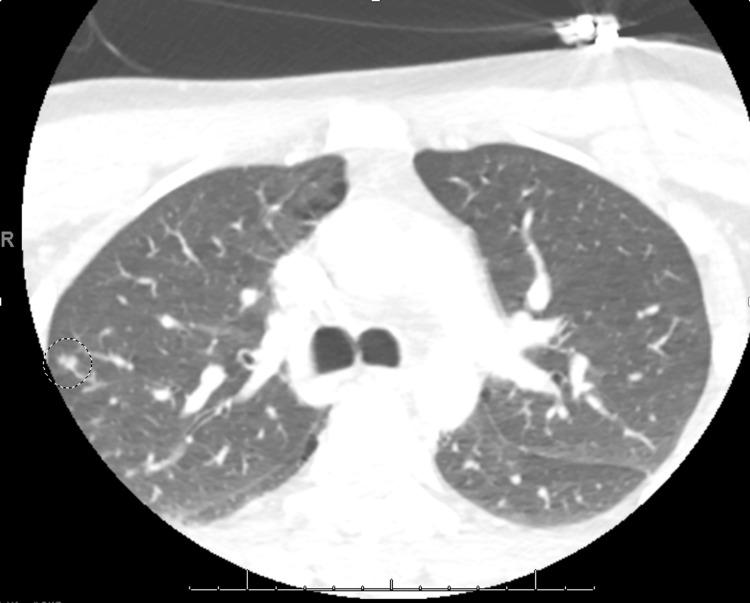

Lemierre's syndrome is a rare and potentially life-threatening complication of head and neck infections, such as bacterial pharyngitis or tonsillitis. It is characterized by the extension of infection into the lateral pharyngeal spaces, leading to subsequent septic thrombophlebitis of the internal jugular vein(s). Although relatively uncommon since the advent of appropriate antibiotic therapy, the incidence of Lemierre's syndrome has increased in the past 15 years, especially among young, healthy adults. This increase is likely attributed to the increasing prevalence of oropharyngeal infections in this population, making an initial diagnosis of Lemierre's syndrome often elusive on presentation. Delayed recognition of this syndrome can result in treatment delays, increasing the morbidity and mortality in this condition. The diagnosis of Lemierre's syndrome is typically confirmed through the identification of thrombophlebitis of the internal jugular vein on radiographic imaging and the isolation of anaerobic bacteria in blood cultures. Treatment involves prolonged antibiotic therapy and, often, anticoagulation. This case report presents a rare complication of bacterial tonsillitis, with initial imaging that demonstrated left peritonsillar phlegmon and subtle micro-occlusions of the left internal jugular vein on early imaging. Within four days, the infection rapidly progressed to complete occlusion of the internal jugular vein with pulmonary septic emboli, culminating in Lemierre's syndrome. This case highlights the importance of early detection and treatment of subtle radiographic findings of thromboses, along with consideration of social determinants of health, in the setting of head and neck infections to avoid rapid progression to Lemierre's syndrome, a disease with an elusive initial presentation and potentially fatal outcomes.

勒米尔综合征是头颈部感染(如细菌性咽炎或扁桃体炎)的一种罕见且可能危及生命的并发症。其特征是感染蔓延至咽旁间隙,继而导致颈内静脉脓毒性血栓性静脉炎。自适当抗生素疗法问世以来,虽然相对不常见,但勒米尔综合征的发病率在过去15年中有所上升,尤其是在年轻健康的成年人中。这种上升可能归因于该人群口咽感染患病率的增加,使得勒米尔综合征在初诊时常常难以确诊。对该综合征的延迟识别可能导致治疗延误,增加该病的发病率和死亡率。勒米尔综合征的诊断通常通过影像学检查发现颈内静脉血栓性静脉炎以及血培养中分离出厌氧菌来确诊。治疗包括长期抗生素治疗,通常还需要抗凝治疗。本病例报告呈现了一例细菌性扁桃体炎的罕见并发症,早期影像学显示左侧扁桃体周围蜂窝织炎以及左侧颈内静脉细微的微血栓形成。在四天内,感染迅速进展为颈内静脉完全闭塞并伴有肺脓毒性栓子,最终发展为勒米尔综合征。该病例强调了在头颈部感染的情况下,早期发现和治疗血栓形成的细微影像学表现的重要性,并考虑健康的社会决定因素,以避免迅速发展为勒米尔综合征,该病初发表现隐匿且可能导致致命后果。